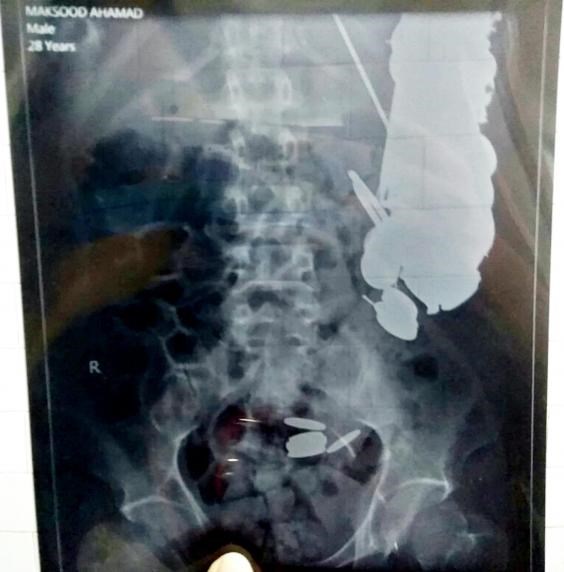

В Индия хирурзи извадиха от пациент 7 килограма метални предмети.

Операцията е била проведена в болница в град Санта. Максуд Хан е постъпил в лечебното заведение с признаци на тежко отравяне. „Решихме да направим ендоскопско изследване и останахме втрещени, когато в стомаха на 35-годишният мъж открихме 263 монети, пирони и гайки”, казва един от лекарите, отбелязвайки, че пациентът най-вероятно страда от психическо заболяване, пише Факти.бг.

Роднините на Хан споделят, че последната година той страда от депресия. Именно тя може и да е виновна пациентът да развие странния навик да поглъща метални предмети.

Лекарите споделят, че операцията е била направена навреме и погълнатите предмети не са успели да нанесат необратими поражения върху органите на индиеца.